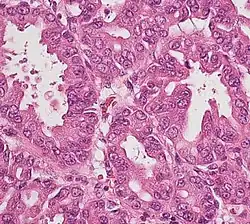

Histopathology

The most common form of pancreatic cancer (adenocarcinoma) is typically characterized by moderately to poorly differentiated glandular structures on microscopic examination. There is typically considerable desmoplasia or formation of a dense fibrous stroma or structural tissue consisting of a range of cell types (including myofibroblasts, macrophages, lymphocytes and mast cells) and deposited material (such as type I collagen and hyaluronic acid). This creates a tumor microenvironment that is short of blood vessels (hypovascular) and so of oxygen (tumor hypoxia).[2] It is thought that this prevents many chemotherapy drugs from reaching the tumor, as one factor making the cancer especially hard to treat.[2][3]

Cancer type | Relative incidence[11] | Microscopy findings[11] | Micrograph | Immunohistochemistry markers[11] | Genetic alterations[11] |

Pancreatic ductal adenocarcinoma (PDAC) | 90% | Glands and desmoplasia | ![]() |

||